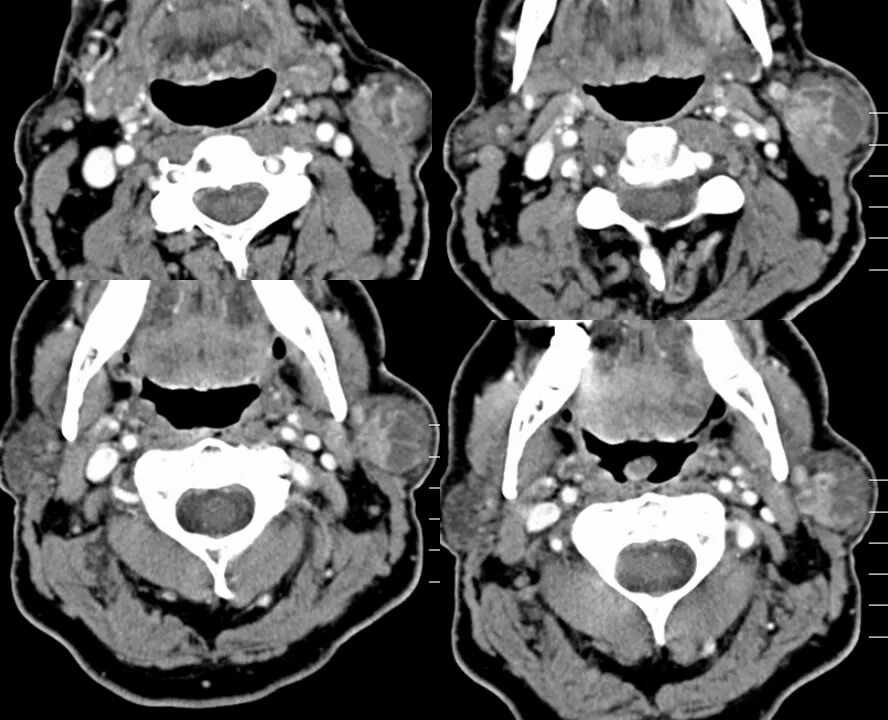

Advanced tumor